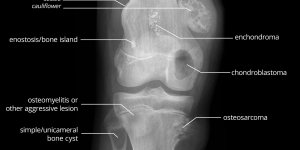

Bone Tumours

Published on Jun 22, 2020

Very informative illustration pertaining to Bone Tumours by Matt Skalski @docskalski on twitter. Bone Tumours – Labelled